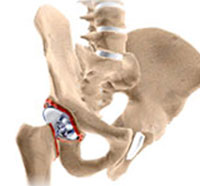

Total hip replacement is a surgical procedure in which the damaged cartilage and bone is removed from the hip joint and replaced with artificial components. The hip joint is one of the body's largest weight-bearing joints, located between the thigh bone (femur) and the pelvis (acetabulum).

Total joint replacement surgery is one of the most advanced successful procedures in patients dealing with severe hip and knee pain. The goal of the surgery is to relieve pain and restore the normal functioning of the joint and help patient resume normal activities.

Revision hip replacement is a complex surgical procedure in which all or part of a previously implanted hip-joint is replaced with a new artificial hip-joint. Total hip replacement surgery is an option to relieve severe arthritis pain that limits your daily activities.